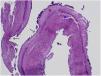

Histological section of proximal oesophagus (haematoxylin-eosin stain, ×4 magnification). Visualization of sloughed-off superficial mucosal layer composed of parakeratotic material with coagulative necrosis (red star), with space between the viable and the necrotic mucosa (blue star). The arrows point at bacteria adhered to the surface of the mucosa.

No evidence of viral inclusion bodies or fungal infection. The intraepithelial eosinophil count was greater than 15 per high-power field in every biopsy sample.